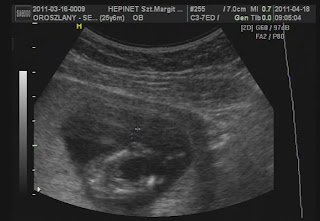

Tegnap túlestünk a kisgenetikán, minden rendben szerencsére :) hoztam is két képet a lurkóról:

Az alsó kép egy talán kukit ábrázol :) Úgy fest, igazam volt, de bele még nem éljük magunkat, majd 18. héten talán okosabbak leszünk :) Én jól vagyok, a fránya hányinger támad be még néha, de ennyi :) Meg fáradt vagyok, sokat és sokszor tudnék aludni... tegnap meg kellett venni az első kismama nadrágomat, mert már egy gatyám sem jött rám... :( de csini vagyok, megdicsértek, milyen nagyot nőtt a pocakom :)